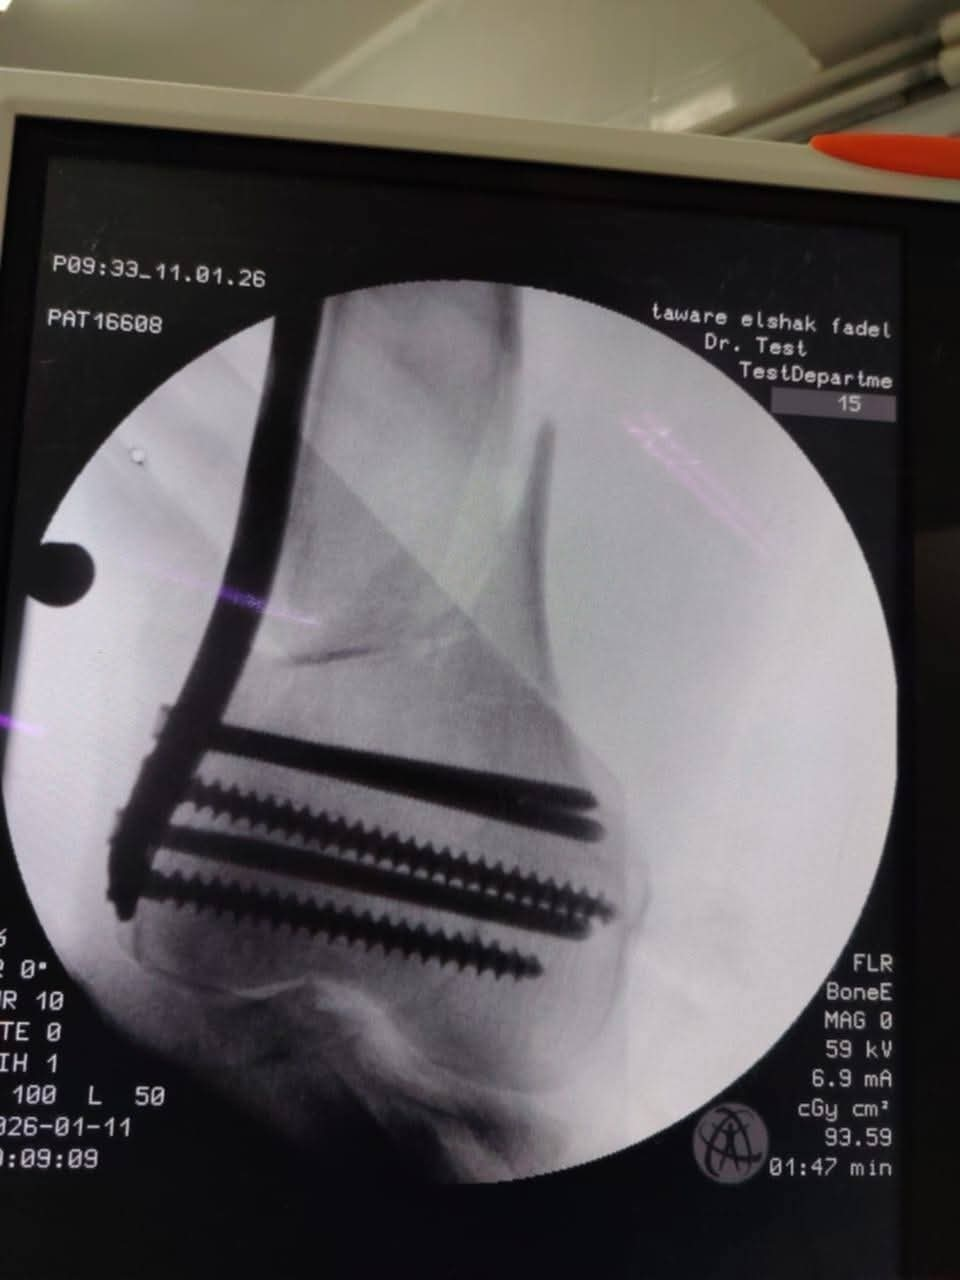

في استمرار لنجاحات المنظومة الطبية داخل مستشفى طوارئ "الشيخ فضل"، نجح الفريق الطبي بقسم العظام في إجراء جراحة دقيقة ومعقدة لرد وتثبيت كسر "متفتت" بأسفل عظمة الفخذ الأيمن لشاب يبلغ من العمر 35 عاماً، إثر سقوطه من علو.

اعتمد الفريق الطبي في هذه الجراحة على تقنية إزاحة الشريحة تحت العضلات (MIPO) عبر فتحات جراحية صغيرة جداً، وهي من أحدث التقنيات العالمية في جراحات الكسور؛ حيث تضمن الحفاظ على الأنسجة والعضلات، وتقلل من احتمالات النزيف والعدوى، مما يسرع من عملية الالتئام وعودة المريض لممارسة حياته الطبيعية بكفاءة عالية.

تم تثبيت الكسر دون الحاجة لفتح جراحي واسع عن طريق استخدام تقنية MIPO، مما يحافظ على التروية الدموية للعظم.

تقليل مخاطر النزيف والالتهابات بفضل التدخل المحدود.

تحسين كفاءة الطرف السفلي وعودة المريض للحركة في وقت قياسي.